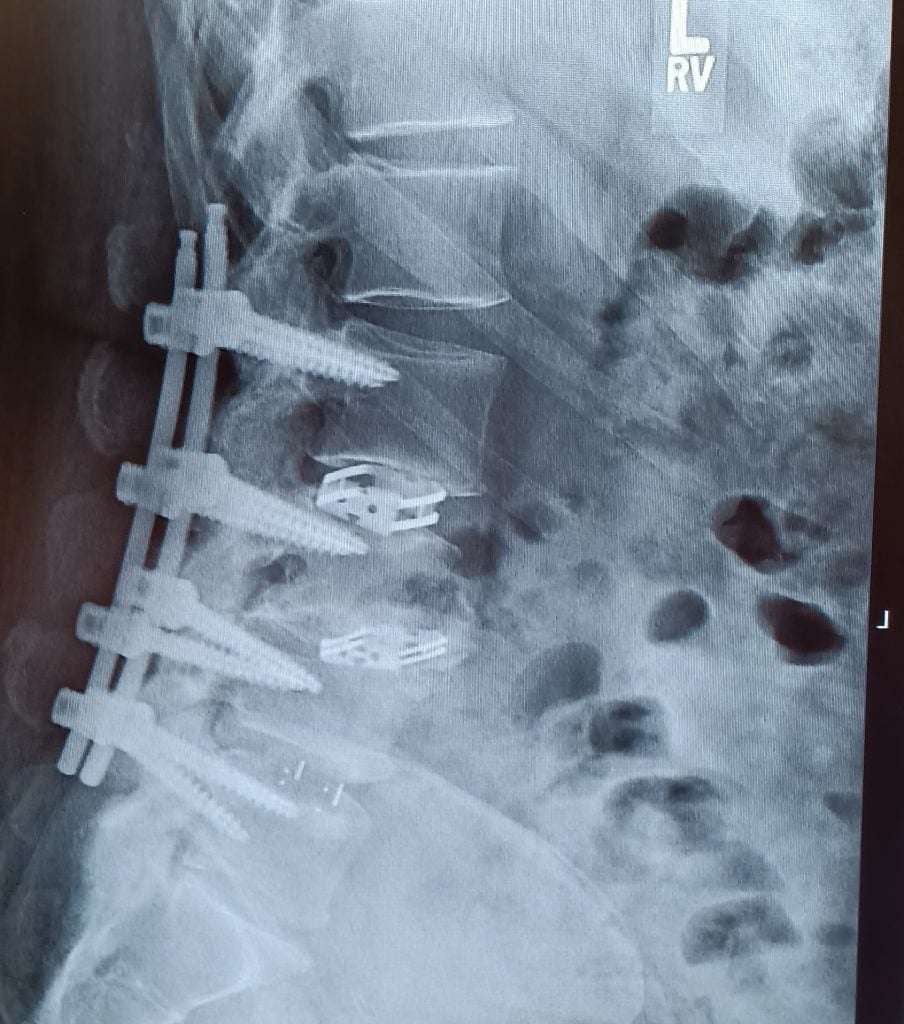

Dr Qureshi strongly suggested spinal fusion of the L4-L5 area of my spine. Not knowing what all that entailed I asked many questions which he easily answered for me. He explained how the minimal invasive surgery works compared to traditional surgery. He even reviewed with me all the images of my spine pointing out what he saw and explained the process to correct it. I’m still amazed as to how just a few small holes in my back and one larger one in my side allowed him to put all surgical equipment in to do the fusion work.